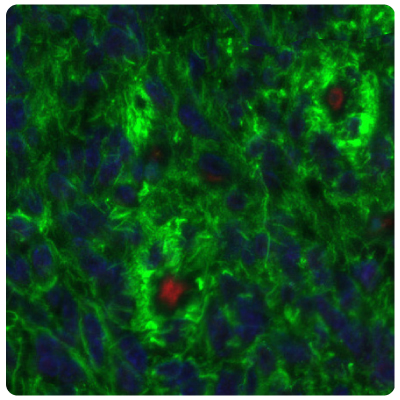

Immunohistochemistry (IHC) plays a vital role in distinguishing between different tumor types. Figures 1 and 2 show some examples of IDH1, ATRX, and GFAP multiplexed IHC-IF staining in different glioma grades.

Figure 2A.ATRX and GFAP in glioblastoma. Multiplexed IHC-IF staining of glioblastoma multiforme showing ATRX (nuclear, in red) and GFAP (cytoplasmic, in green) immunoreactivity in tumor cells using Anti-ATRX antibody and Anti-GFAP antibody. Nuclei were counterstained with DAPI (in blue).

Figure 2B.ATRX and IDH1 in glioblastoma. Multiplexed IHC-IF staining of glioblastoma multiforme showing ATRX (nuclear, in red) and IDH1 (cytoplasmic, in green) immunoreactivity in tumor cells using Anti-ATRX antibody and Anti-IDH1 antibody. Nuclei were counterstained with DAPI (in blue).